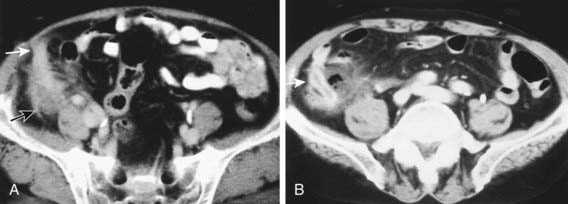

CT scan has been the gold standard imaging study for evaluating children with suspected appendicitis. CT examination can be performed in many ways, including standard CT scan, helical CT scan, with or without oral and intravenous contrast, examination of both the abdomen and pelvis or pelvis alone, focused appendiceal CT scan, and focused appendiceal CT scan with rectal contrast. All of these techniques have demonstrated >95% sensitivity and specificity for acute appendicitis. Findings on CT scan consistent with appendicitis include a distended thick-walled appendix, inflammatory streaking of surrounding mesenteric fat, or a pericecal phlegmon or abscess (Figs. 335-3 and 335-4).

image

Figure 335-4 A, Precontrast-enhanced CT reveals an appendicolith (arrow) in perforated appendicitis. B, Postcontrast-enhanced CT (1 cm below the level in A) reveals intraluminal air in the appendix (curved arrow) associated with ileal wall enhancement in perforated appendicitis.

(From Yeung KW, Chang MS, Hsiao CP: Evaluation of perforated and nonperforated appendicitis with CT, J Clin Imag 28:422–427, 2004.)

Appendicoliths are more readily demonstrated on CT scan than on plain radiographs. CT scan is also useful in advanced appendicitis to identify and guide percutaneous drainage of fluid collections and identification of an inflammatory mass, which might prompt a plan for initial nonoperative management.